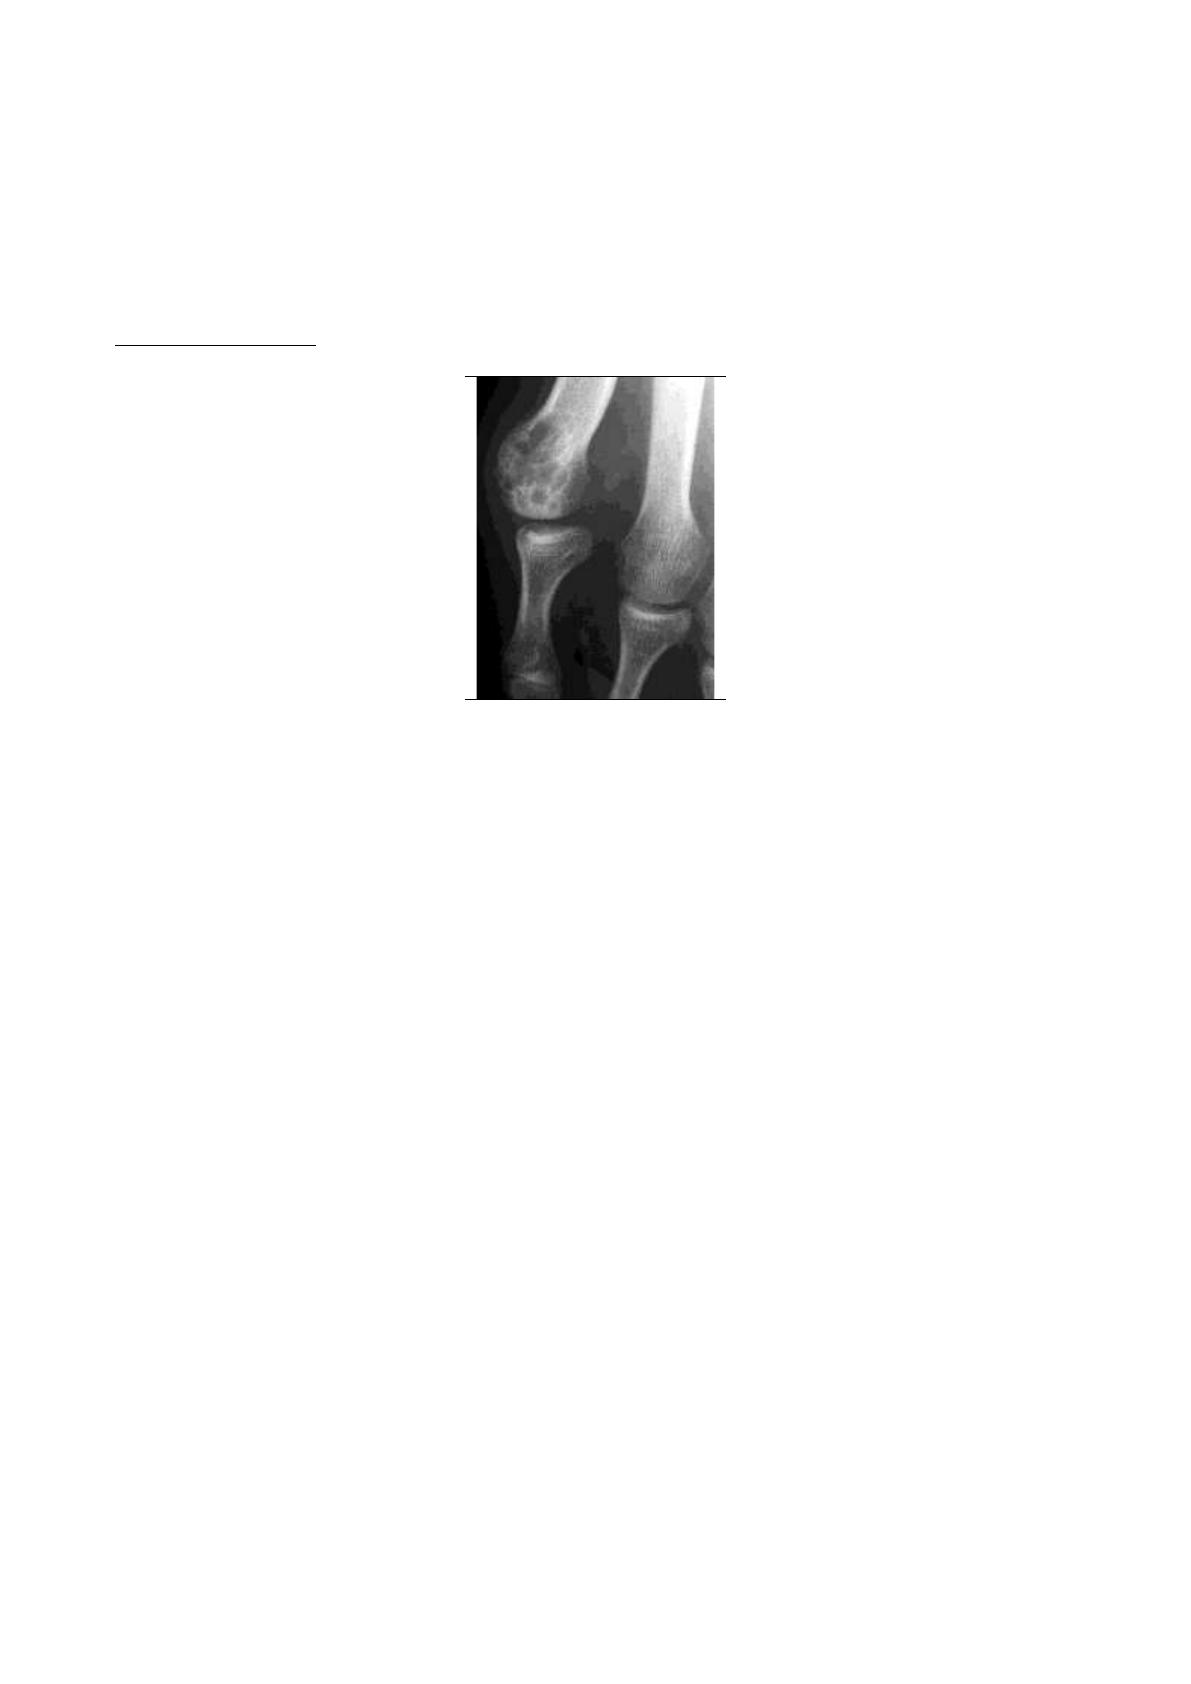

Dans sa forme typique, c'est une polyarthrite acromélique touchant les mains et les pieds, mais

respectant les articulations inter-phalangiennes distales (IPD). Elle a une nette tendance à la

symétrie. Les douleurs siègent aux poignets, aux métacarpo-phalangiennes (MCP) et aux

interphalangiennes proximales (IPP) mais aussi aux avant-pieds où elles prédominent aux

métatarsophalangiennes (MTP). Ces douleurs ont un caractère inflammatoire, avec recrudescence

dans la deuxième moitié de la nuit. Elles s'accompagnent d'un enraidissement matinal plus ou

moins prolongé. L'arthrite des IPP cause un gonflement des doigts en fuseau. Aux mains, l'atteinte

prédomine souvent aux 2 e et 3e MCP, aux pieds aux 4 e et 5 e MTP. Aux arthrites, sont souvent